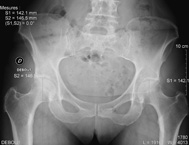

| des hanches, des genoux et des pieds en cas de douleurs. |